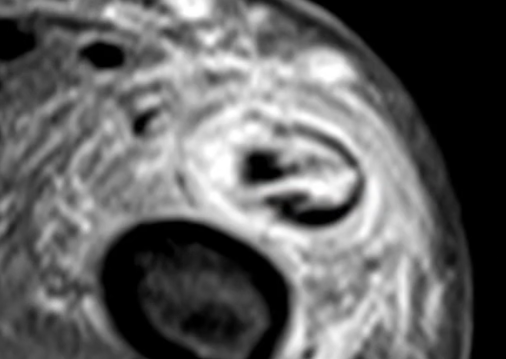

Tendinose et Ténosynovite